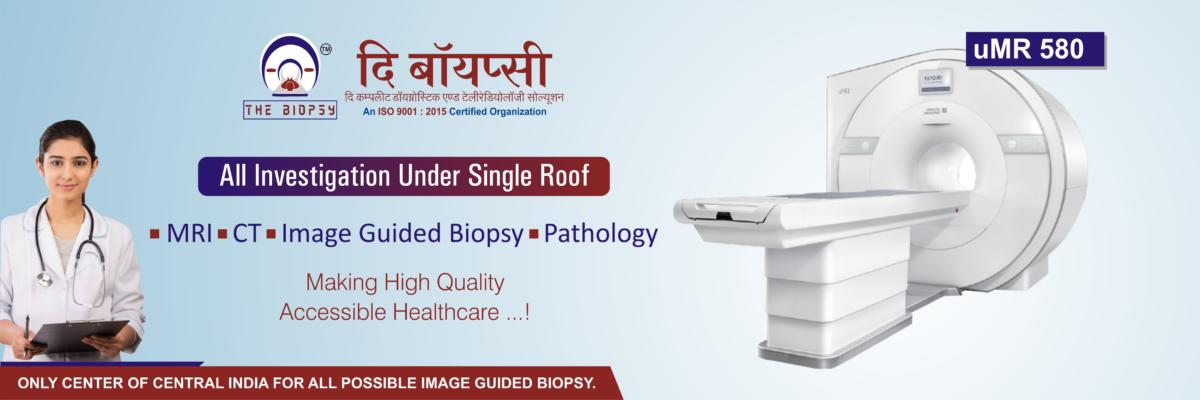

The Biopsy is a premier high-quality diagnostic center specializing in advanced radio-diagnostic imaging and interventional radiology. We are committed to delivering precise, reliable, and cutting-edge diagnostic solutions using the latest MRI and CT scan technology.

✅ Clinical Cross-Sectional Radiology (CT & MRI)

✅ Interventional Radiology, including Vascular & Non-Vascular Procedures

✅ Image-Guided Biopsies & Pain Management

✅ Cardiac MRI & Tumor Imaging Protocols

With a patient-centric approach and state-of-the-art equipment, we aim to set new benchmarks in diagnostic excellence, ensuring accurate diagnosis, timely interventions, and superior patient care.

Advanced Level and Latest generation Diagonostic Machine Provide.

MRI- Machine

CT-Scan & X-Ray